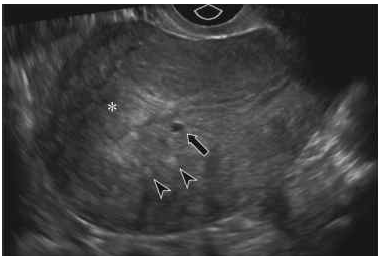

Paciente, 36 anos, relata ocorrência de sangramento aumentado nos últimos dois anos, desde a LT. Tem apresentado coágulos, cólicas e duração de 10 dias do sangramento. Nuligesta. É hipertensa, obesa e tem DM tipo I. Consultou um médico que indicou histerectomia, mas deseja uma segunda opinião, pois não deseja realizar cirurgia. Traz hemograma, mamografia e citopatológico cervical com ASCUS, e ultrassom com a imagem abaixo.

Qual a conduta mais adequada para este caso?